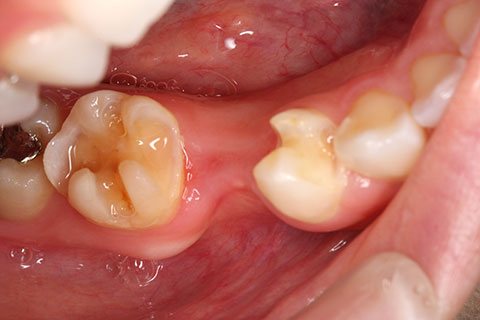

ジルコニアブリッジの症例1

- 年齢・性別

- 30歳男性

- 治療期間

- 1ヶ月

- 抜歯

- 右下5番欠損

- 治療費

- 16.5万円(税込み)

- 備考

- 歯質の削除量を最小限に抑えるブリッジ治療

- 治療内容

- 欠損部位の隣接歯を削合後、セメント合着

- 施術の副作用(リスク)

- 知覚過敏、歯髄炎、荷重負担